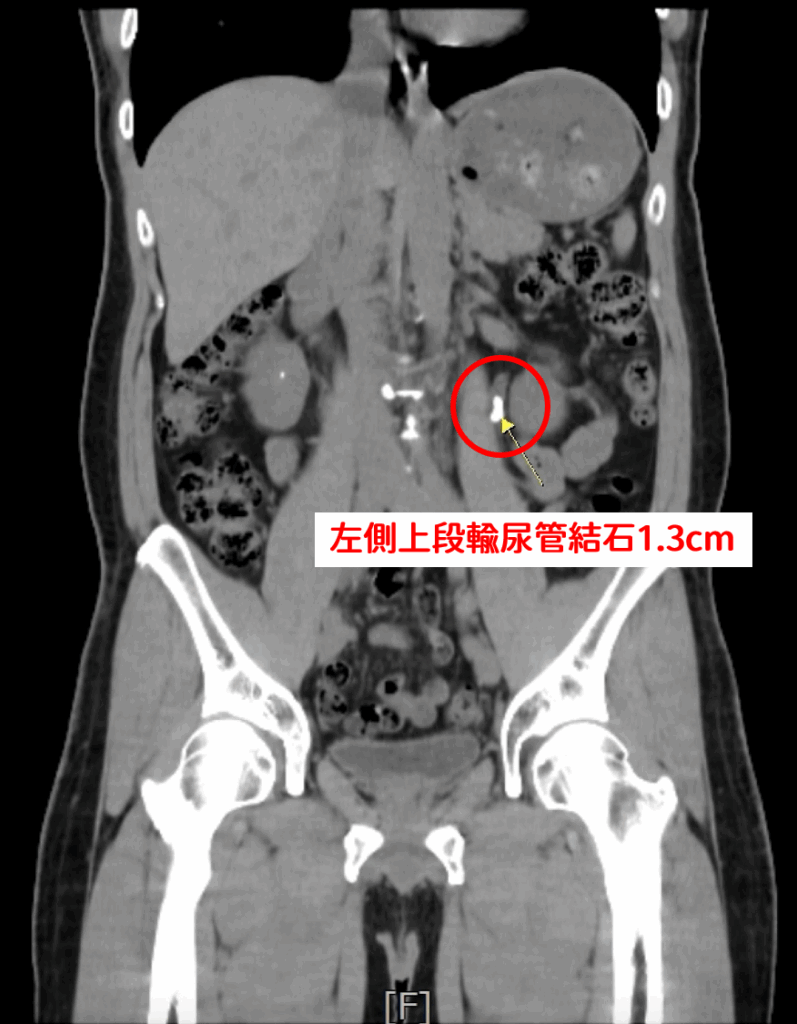

一名45歲男性,因血尿及左側腰部疼痛持續數週就醫,求診中國醫藥大學新竹附設醫院泌尿科醫師王曦賢,先經X光檢查,發現患者左側腎盂輸尿管交接處約有1.3公分結石,合併左腎多顆小結石。初期接受兩次體外震波碎石術治療,但門診追蹤顯示結石未明顯改善,經醫病溝通後,改採軟式輸尿管鏡逆行性腎臟內取石手術,處理約36顆結石,手術約2小時,術後隔天即可出院,病患不再疼痛,半年門診追蹤即可。

泌尿科醫師王曦賢指出,該個案術前進一步安排電腦斷層檢查時,意外發現患者右側腎臟與輸尿管亦有細小結石。不宜腎臟兩側執行體外震波碎石術,未來可能造成結石雙側阻塞,嚴重時恐導致腎功能受損,甚至需緊急洗腎。因此在與患者充分溝通後,決定進行軟式輸尿管鏡逆行性腎臟內取石手術,一次解決雙側結石問題,降低風險。該患者一次手術後,處理約36個腎結石。